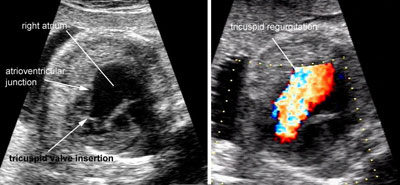

Ebstein malformation of the tricuspid valve

Legend:Ebstein malformation of the tricuspid valve: the leaflets of the tricuspid valve are displaced apically compared to the atrioventricular junction and there is massive tricuspid regurgitation

Tricuspid dysplasia

Legend:Cardiomegaly, enlargement of the right side of the heart and right atrium in particular, massive regurgitation across a normally inserted tricuspid valve